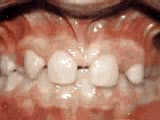

Phase One

Before

AfterThis boy’s parents were concerned about both aesthetics and the health of the erupting permanent teeth when they brought him to the orthodontist at age eight. The lower front teeth were crowded and touching the palate, and the upper front teeth were extremely displaced from their normal positions. After 12 months of Phase-One treatment with an expander and partial braces, the patient’s appearance and dental function were vastly improved.